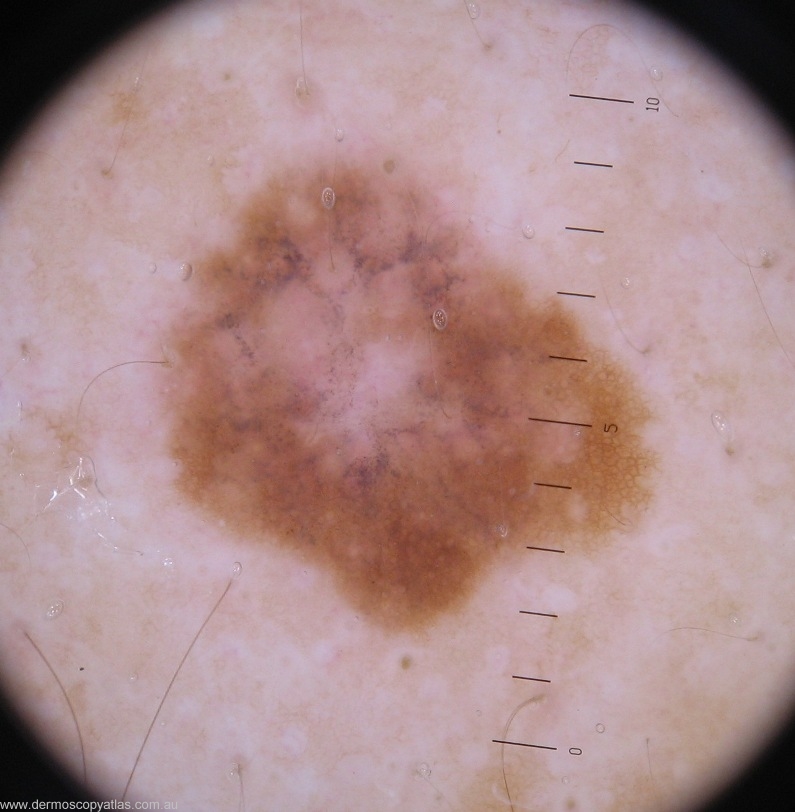

Case 2. A 38 yr old male with a history of several BCC excised (elsewhere), presented with a recurrent lesion on the nose (BCC), incidentally this lesion on the back was found during a full skin check, both the patient and his wife were unaware of it. Consider the following options- Lichen planus like keratosis,Solar lentigo, Banal nevus, Dysplastic nevus, Melanoma or Other.

Question: What is your clinical diagnosis?

Question: What is your dermatoscopic diagnosis?

Question: What do you think the histology will show?